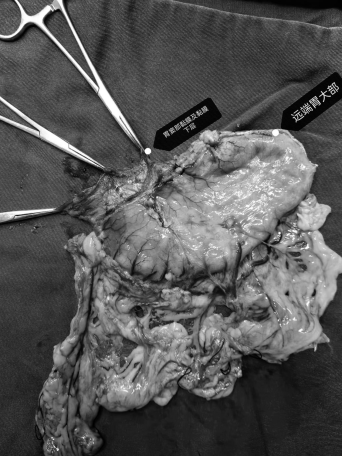

针对张女士的病情特点,科室组织了多轮讨论,最终确定手术方案:拟采用Bancroft法胃大部切除术,切除至少2/3的胃减少胃酸分泌以降低术后十二指肠溃疡复发风险,并旷置十二指肠溃疡,联合胃空肠Roux-en-Y吻合术重建消化道,同时术中置入空肠营养管,为术后早期肠内营养提供“绿色通道”,有效预防吻合口漏。手术过程中,医护团队精准操作,顺利完成胃部切除、消化道吻合及营养管置入,为患者术后康复奠定了坚实基础。

(术中情况)